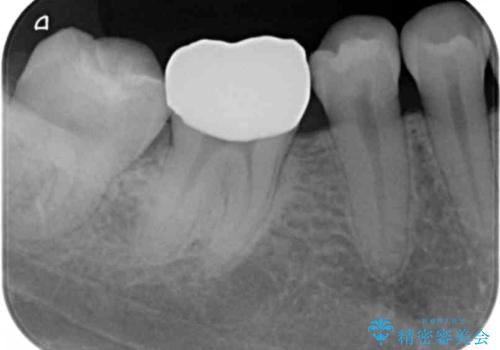

- 右下の奥歯が欠けたとのことで来院されました。

診てみると奥歯の詰め物が欠けていることが分かりました。

噛みしめが強く、元の詰め物の大きさが大きかったため今回は被せ物での治療をすることとなりました。

欠けた詰め物をすべて取り除くと深いところに取り残された虫歯を発見しました。

虫歯の除去後は残った歯の厚みが薄くなっていたため、今後の破折リスクを考慮してクラウンでの修復処置となりました。

虫歯が深く歯の神経の炎症が予想される箇所には鎮静作用のあるセメントを敷き、経過をみた後に被せ物をセットしました。

写真・レントゲン画像からもわかる通り、適合の良いクラウンを入れることができました。